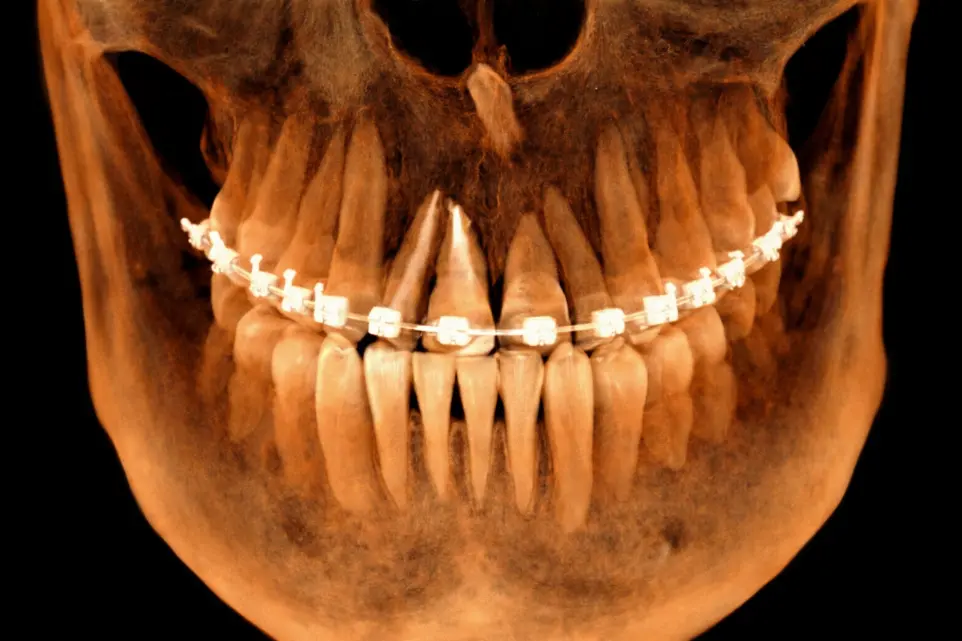

TOMOGRAFÍA DE IMPLANTES

Cuando es necesario evaluar las condiciones óseas de los rebordes alveolares.